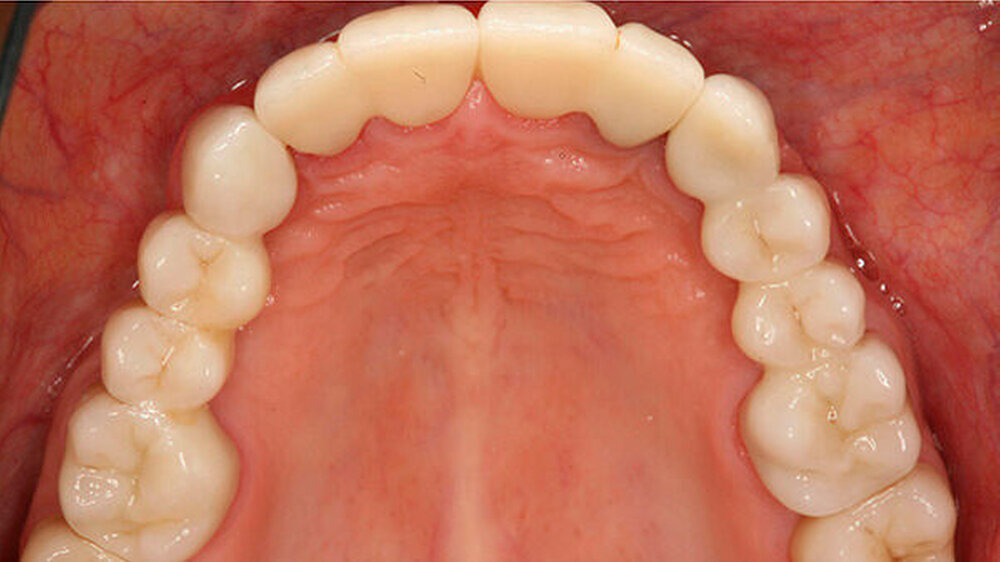

Beispiele für individuellen ZE

Die Jahrestagung der Deutschen Gesellschaft für Prothetische Zahnmedizin und Biomaterialien (PGPro) in Ulm geht der Frage nach, welche Versorgungskonzepte - mit guten Langzeitergebnissen - individuell und preiswert machbar sind. Gute Beispiele finden Sie in unserer Bilderstrecke!